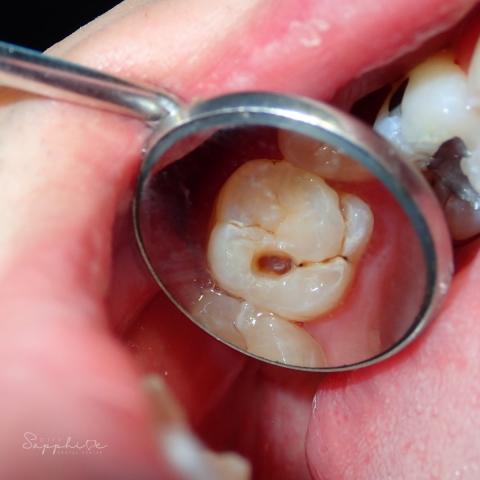

Upon examination, the affected molar shows a clear dental cavity at the occlusal (chewing) surface. The darkened area indicates enamel breakdown and dentin exposure, which means the decay has already penetrated past the outer protective layer of the tooth.

Diagnosis:

Condition: Dental Caries (Tooth Decay)

Stage: Moderate — decay reaching dentin layer

Affected Area: Posterior molar (chewing surface)

Recommended Treatment: Tooth restoration (filling) or possible root canal therapy if pulp involvement is detected